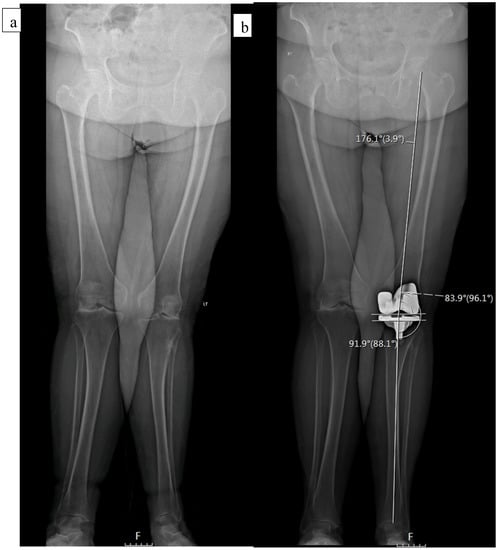

| MPTA | 84.33 (3.08) | 89.32 (2.74) | <0.001 | 86.32 (3.11) | 87.05 (3.11) | 0.127 |

| LDFA | 90.10 (3.8) | 86.64 (3.6) | <0.001 | 84.94 (4.1) | 83.59 (4.40) | 0.036 |

| HKA * | −10.78 (4.79) | 5.92 (4.26) | <0.001 | −2.83 (2.81) | 1.36 (4.18) | <0.001 |